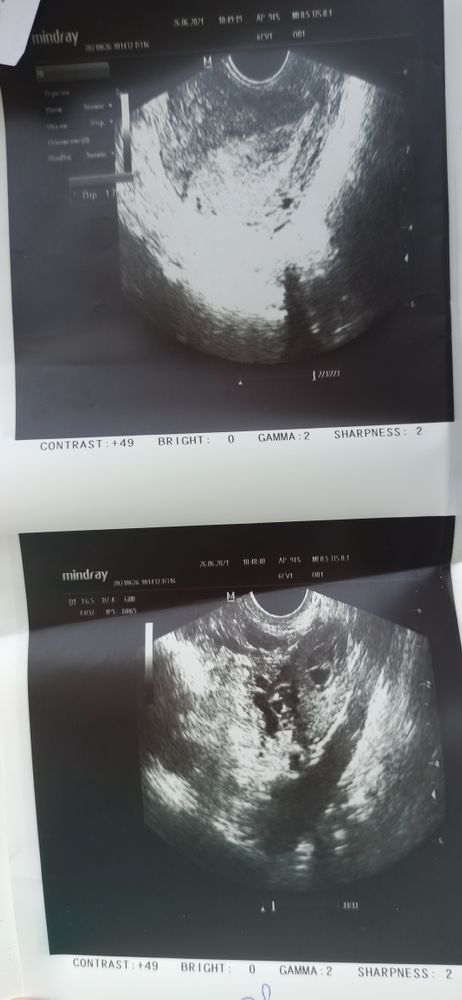

Узи в 5 недель

10 дней задержки, наверное уже 6ая акушерская, странно, что матка не увеличена и ПЯ толком не визуализируется. А хгч не сдавали? Может О и/или И поздние, может хгч еще не столь велик, чтобы ПЯ нормально увидеть? Тесты давно полосатые, яркие?

Елена, мне просто кажется, что на фото узи есть пя

Аня, возможно, но на таких размерах четко идентифицировать невозможно, пя или не пя. Это же просто образование, определенным образом отражающее звук. Нужны внятные размеры в несколько мм для идентификации. Сходите, сдайте хгч, многое понятнее будет.

Вот мое узи ровно в 5 акушерских,в заключении поставили эмбриональный срок -3 недели ( от зачатия) Изображение

Марина, ну, вот у Вас все понятно. И пя хорошо видно. Нет, у меня нет вообще никаких размеров. Но мне кажется на моем фото тоже есть пя. Я в шоке от того как мне сделали узи

Аня, может УЗИ переделайте,так то вроде и похоже на пя на снимке,но возможно и не оно, вообще странно что вам осмотр описали,а само УЗИ нет

Как нет? А что это тогда на фото узи?) По-моему очевидно, что там пя)! Тем более в заключении написали... Странные

Аня, это описание осмотра,а где данные УЗИ? По фото мне кажется видно плодное яйцо.

У меня есть узи в 4 недели и 3 дня, пя хорошо видно, переделайте узи в другом месте? Я думаю найдут. Главное, чтобы не вб.

Вы рано пошли. Официально Б могут поставить при определённом размере пя, если оно совсем маленькое теоретически это может быть сгусток или полип какой .